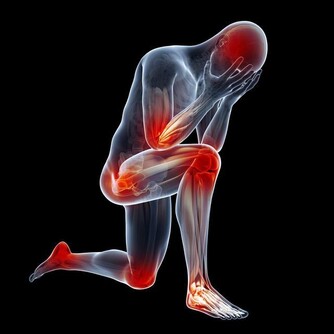

肥胖真的超燒錢!肥胖有可能是你花了很多錢吃喝,也有人會花很多錢來減肥,肥胖甚至會引起很多疾病,而且去治療這些疾病,健保還得給付;醫界更預估,到了2020年時,健保預算的1/3是用來給付因為肥胖所引起的疾病。 高血壓+高血脂+糖尿病+心血管疾病+癌症 有哪些疾病是因為肥胖所引起、會需要用到健保來看病的呢?天主教聖馬爾定醫院家庭醫學科主任陳志誠指出,肥胖會出現代謝症候群,進而引起高血壓、高血脂、糖尿病,並且也會造成心血管的問題,肥胖甚至會增加一些癌症的風險,例如大腸癌及乳癌,肥胖都是危險因子。 退化性關節炎+對磨疹+淋巴水腫+睡眠呼吸中止症 陳志誠主任進一步指出,肥胖還會使得膝關節和髖關節負擔大,以致出現退化性關節炎,皮膚也會因為容易在皺摺處引起對磨疹或是感染,增加淋巴性水腫的可能性,肥胖更可能產生睡眠呼吸中止症,影響睡眠品質。 成人過重及肥胖盛行率為38% 根據世界衛生組織研究報告顯示,全球有將近1/3成人、1/4孩童過重,總計目前全球肥胖或過重的人口超過21億。而根據衛福部所進行的2013年「國民營養健康狀況變遷調查」結果顯示,成人過重及肥胖盛行率為38%;也就是說,不到三個成年人中,就有一人過重或是肥胖;醫界並預估,到2020年時,將有1/3健保預算,會用來給付因為肥胖所引起的相關疾病診療費用。。 飲食與運動是減重不二法門 因此,減重除了能改善體態之外,更重要的是能預防諸多疾病,而飲食與運動則是減重的不二法門;陳志誠主任則是強調,減重要成功,其關鍵就是要先找到自己想改變的原因,而且慢慢的把不好的習慣一個一個改過來,不求速效,而是考慮可以維持多久! 健康醫療網: http://www.healthnews.com.tw/news/article/29601